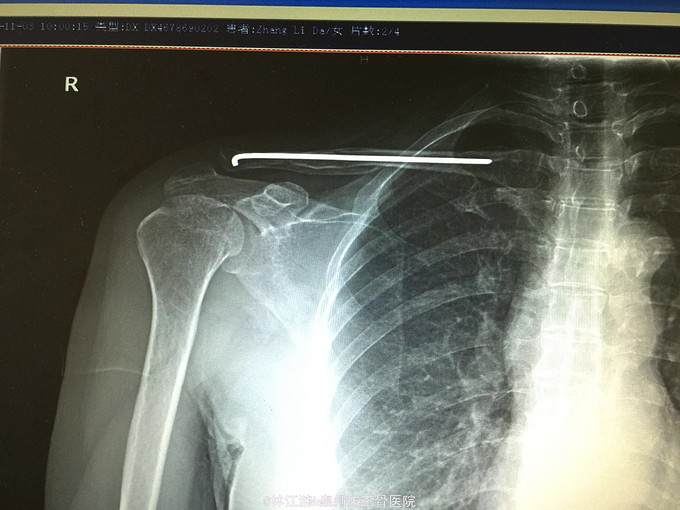

右锁骨粉碎性骨折闭合复位克氏针内固定术

摔伤致右肩部肿痛活动受限3小时

右锁骨部肿胀,锁骨中段压痛明显,可及明显骨擦感,右肩活动受限,肢端感觉活动正常

右锁骨粉碎性骨折 行闭合复位克氏针内固定术